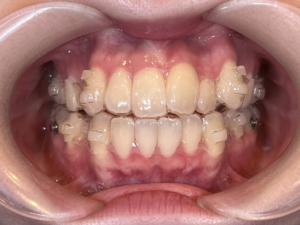

ストレスで歯並びが悪化する?悪循環のメカニズムとマウスピース矯正で断ち切る方法を解説

中でも近年人気を集めているのが「マウスピース矯正」。

✅ マウスピース矯正が選ばれる理由

透明で目立たないから、仕事やプライベートでも安心

装着中は歯が守られるため、くいしばりによるダメージも軽減

歯の動きをコントロールすることで、噛み合わせや筋肉のバランスが整う

部分矯正も可能で、気になる前歯だけ治したい人にも◎